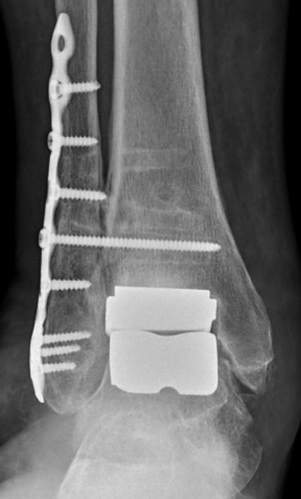

TOTAL ANKLE REPLACEMENT :: ORIF CALCANEUS :: ORIF ANKLE FRACTURE DISLOCATION :: COMPLEX BUNION AND LESSER TOE CORRECTION :: TALUS FRACTURE -1 :: TALUS FRACTURE -2 :: LISFRANC REPAIR :: COMPLEX TRIPLE ARTHRODESIS 1 :: COMPLEX TRIPLE ARTHRODESIS 2 :: MINIMALLY INVASIVE BUNION REPAIR 1 :: MINIMALLY INVASIVE BUNION REPAIR 2 :: ARTHROSCOPIC CARTILAGE REPAIR :: TENEX SPUR DEBRIDEMENT :: Haglunds Debridement and Achilles Repair